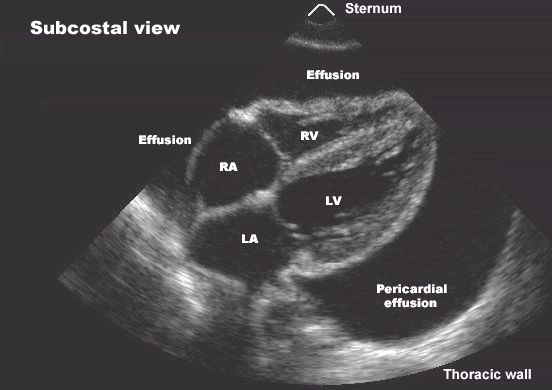

Pericardial Effusion

Echocardiogram showing fluid surrounding the heart.

- If performed in patients with good acoustic windows, echocardiography will accurately detect all pericardial effusions and provide important information about their size and hemodynamic importance.

- Echocardiography is less reliable than MRI or CT in detecting pericardial thickening or small loculated effusions, but it is still extremely useful in these conditions.

- Echo free space around heart.

- Accumulation of pericardial fluid creates an anechoic space between the posterior left ventricular wall and the anterior parietal pericardium. In larger effusions, a similar echo-free space exists between the anterior right ventricular wall and the anterior parietal pericardium and chest wall.

- The technique is semi quantitative: very small effusions (50 -100 ml) are imaged only posteriorly, with separation of pericardial and epicardial echoes only in systole; small to moderate effusions (100 - 300 ml) are imaged only posteriorly throughout the cardiac cycle; and large effusions (300 ml) are imaged both anteriorly and posteriorly. Because of the oblique pericardial sinus, the echo-free space disappears behind the left atrium unless massive pericardial effusion is present.

- Diastolic collapse of right ventricle.

- Dilated inferior vena cava.